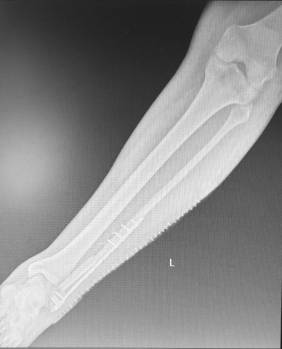

El paciente intervenido, de 49 años, estaba afectado por una fractura de peroné en la región de la articulación del tobillo, consecuencia de un accidente de tráfico hace ya 3 años, que no terminaba de evolucionar bien tras varias alternativas quirúrgicas. Así, tras apostar primero por fijar el hueso con placas y tornillos y posteriores injertos de hueso libre de la cadera, los focos de fractura seguían sin consolidar, por lo que, como recuerda la especialista, "el paciente sufría una importante inestabilidad en la función del tobillo y estaba sujeto a tratamiento con mórficos por mucho dolor en la pierna".

La tercera y última alternativa, nada menos que un trasplante microvascular del peroné de la otra pierna del paciente, ha supuesto un antes y un después en la resolución de este caso. Tanto que se ha traducido en un alta hospitalaria del paciente tras una evolución satisfactoria que le han permitido regresar a su domicilio tan solo con unas muletas y una sencilla pauta de tratamiento antiinflamatorio.

Una recuperación que el equipo del Dr. Alonso seguirá conforme a protocolo durante los próximos meses. Y un éxito que, en palabras de la Dra. Pingarrón, ha sido posible "gracias a un estudio y planificación tridimensional de la intervención previos a la misma mediante modelos estereolitográficos con el que los cirujanos pudieron identificar y programar las guías exactas de corte y diseñar el segmento preciso de peroné a trasplantar, y ante todo a la colaboración y trabajo en equipo".

Asimismo, y "dado que los vasos sanguíneos del peroné de la pierna afectada estaban muy deteriorados de cara a la anastomosis vascular por el tiempo transcurrido desde el accidente y los dos primeros abordajes quirúrgicos -continua la jefa del Servicio de Cirugía Oral y Maxilofacial del centro-, tuvimos que realizar una anastomosis término-lateral a los vasos tibiales para conectar extremos vasculares de diferente calibre, lo que terminó de consolidar el éxito de la intervención".

El resultado habla por sí solo: tan solo 24 horas de vigilancia intensiva en la UCI y una semana de ingreso hospitalario después de la intervención, el paciente ha sido dado de alta con un pronóstico favorable que confirma que la experiencia atesorada y compartida entre especialidades quirúrgicas -ambos servicios ya habían trabajado juntos previamente, en este caso con motivo de una fractura de antebrazo-, junto con la de la Unidad de Cuidados Intensivos y Anestesiología, sumado al enfoque multidisciplinar y personalizado de cada caso, pueden arrojar innovadores abordajes que redunden en claros beneficios para los pacientes.